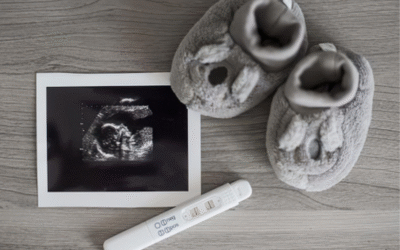

Welcoming Your Newest Family Member: A Guide to Complete Maternity Care

The journey toward parenthood is one of the most transformative...